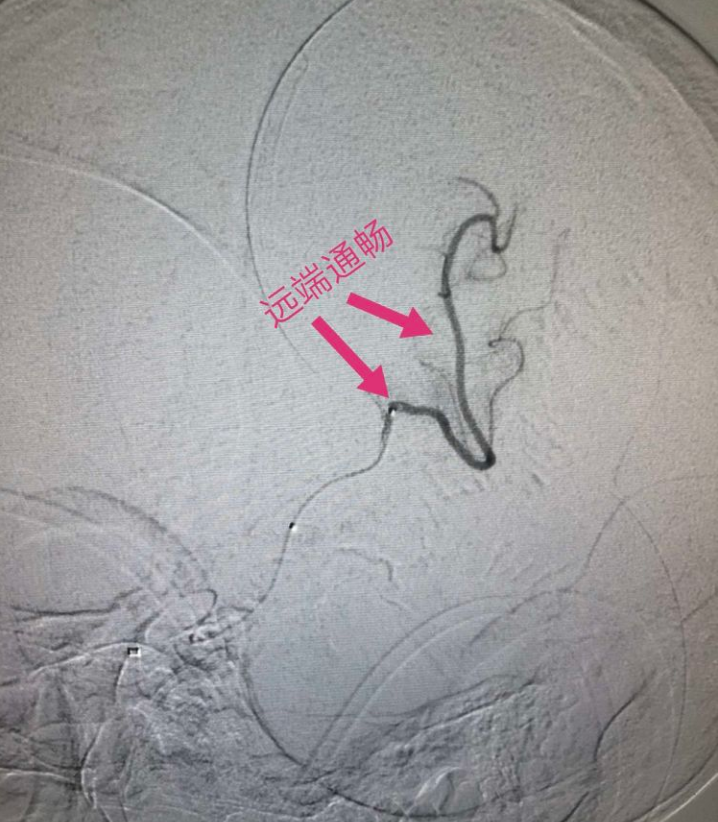

远端血管通畅

释放支架